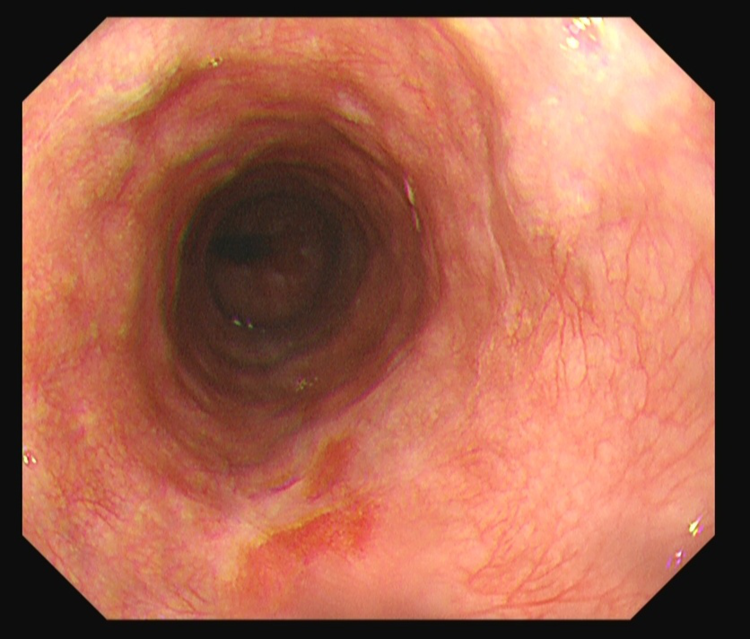

术前内镜下白光示:不规则片状黏膜略粗糙,表面发红

内镜NBI示:病变黏膜粗糙,呈茶褐色改变